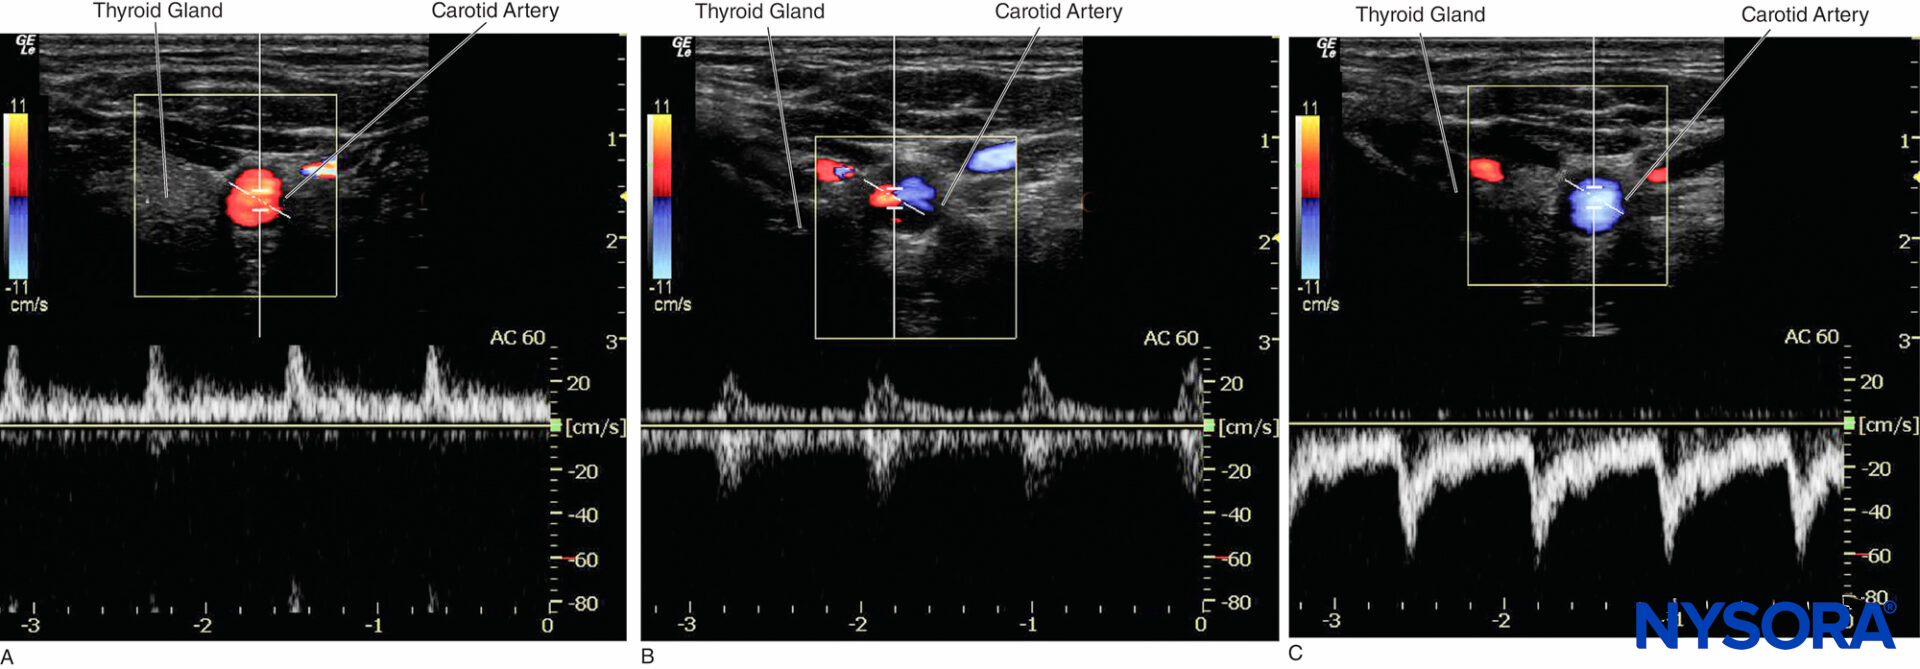

Color Doppler produces a color-coded map of Doppler shifts superimposed onto a B-mode ultrasound image. Blood flow direction depends on whether the motion is toward or away from the transducer. Selected by convention, red and blue colors provide information about the direction and velocity of the blood flow. According to the color map (color bar) in the upper left-hand corner of the figure (Figure 12), the red color on the top of the bar denotes the flow coming toward the ultrasound probe, and the blue color on the bottom of the bar indicates the flow away from the probe.

B-mode ultrasound image. Selected by convention, red and blue colors provide information about the direction and velocity of the blood flow. (Adapted with permission from Hadzic A: Hadzic’s Peripheral Nerve Blocks and Anatomy for Ultrasound-Guided Regional Anesthesia, 2nd ed. New York: McGraw-Hill, Inc; 2011.)

Figure 13. Color Doppler mode is used to detect the direction of the blood vessel.

In ultrasound-guided peripheral nerve blocks, color Doppler mode is used to detect the presence and nature of the blood vessels (artery vs. vein) in the area of interest. When the direction of the ultrasound beam changes, the color of the arterial flow switches from blue to red, or vice versa, depending on the convention used (Figures 13, 14A, 14B, and 14C). Power Doppler is up to five times more sensitive in detecting blood flow than color Doppler, and it is less dependent on the scanning angle. Thus, power Doppler can be used to identify the smaller blood vessels more reliably. The drawback is that power Doppler does not provide any information on the direction and speed of blood flow (Figure 15).

Figure 14. A: Carotid artery displays a red color when the blood flows toward the transducer. B: Carotid artery displays ambiguous color at a 90° Doppler angle; the equal waveform can be seen on both sides of the baseline. C: Carotid artery displays blue color when the blood flows away from the transducer.